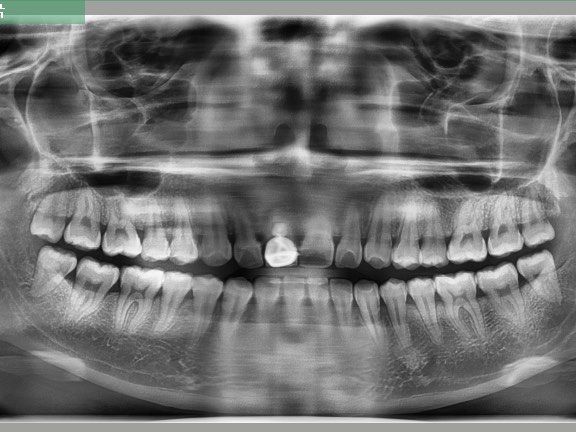

【讨论】一例不良修复体